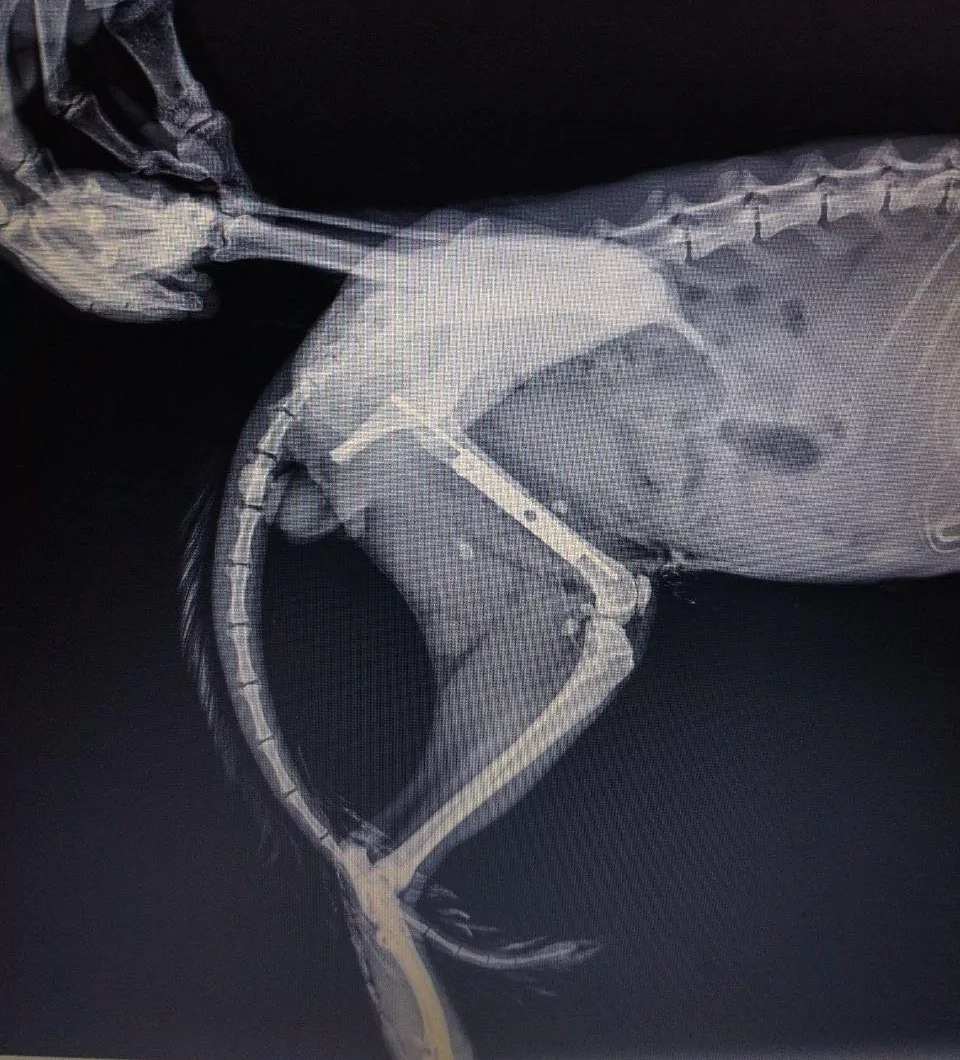

За їхніми даними, дворічного кота на ім’я Серьожка доставили до Харкова військові. Під час огляду у нього виявили відкритий перелом правого стегна, а також рвані рани тазових кінцівок.

Лікарі провели складну операцію — остеосинтез стегна — та призначили інтенсивну терапію. Після втручання тварина поступово почала відновлюватися.